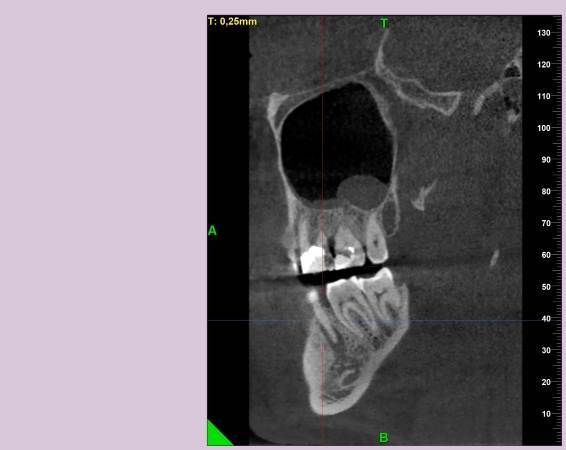

КТ от 04.03.2024

69273_3.jpg.f56a31dc1d8d53085767a9a52915128c.jpg69273_4.jpg.f9ec255bedbdb9fde8159318d3cb1fd9.jpg69273_5.jpg.36a7a942d403dd2eb062e5a4b2b58a52.jpg69273_6.jpg.492d3fbca3808fbdf58c86056b2fe0c3.jpg69273_7.jpg.f9bfdd5d593504dc7bd3710ece18aa4f.jpg69273_8.jpg.853e2342e6f2329a2e89c8939c2aad6f.jpg69273_11.jpg.e495813d50bf007f7165bf5f5dfec4b3.jpg69273_12.jpg.49b3cf66b4dd26b5cd68a91b2684e402.jpg69273_13.jpg.5d61b621b8e8b2c473ad6a8aca42502d.jpg

Добрый день! В данный момент прохожу лечение 46 зуба. Улучшений нет, поэтому возникли сомнения в тактике лечения выбранной моим стоматологом.

Предоставил доктору КТ от 04.03.2024(приложено ниже). Доктор посетовала на то, что в 3D не очень умеет, только панорамные снимки. Новый снимок, или КТ не предложила сделать. Вскрыла полость зуба, прочистила каналы, и заложила "Пульпосептин"(с ее слов), закрыв временной пломбой. Пломба была странная шершавая, похожая на высохшую зубную пасту, и за два дня наполовину "сточилась".

Лекарство было извлечено, и каналы запломбированы гуттаперчей. Доктор предупредила, что зуб будет болеть, и прийти я должен после того, как зуб "успокоится", болевые ощущения пропадут. На третий день десна под зубом вспухла, и начала сочиться сукровица. Я решил сделать новое КТ(28.05.2024), и с результатом сходить в другие клиники для консультации. В первой мне сказали, что доктор не должна была начинать лечение, потому, что зуб идет под удаление. Во второй клинике, что попытаться вылечить можно, но изначально были допущены ошибки в лечении, и надо переделывать.

Что-то можно сделать с 46 зубом для сохранения, или он должен быть удален?